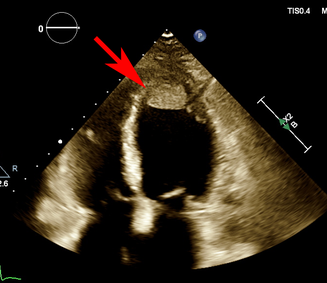

A 41‐year‐old G1P1 woman presented with two days of dyspnoea four weeks postpartum. She had an uncomplicated caesarean delivery at 39 weeks’ gestation in the setting of uterine fibroids, and she was breastfeeding. Her medical history was otherwise unremarkable. An electrocardiogram demonstrated sinus rhythm with anterolateral T‐wave inversion. A computed tomography (CT) pulmonary angiogram demonstrated no pulmonary embolus but pleural effusions and cardiomegaly. A transthoracic echocardiogram (TTE) demonstrated a left ventricular ejection fraction (LVEF) of 19% (normal range, ≥ 50%), left ventricular end‐diastolic diameter (LVEDD) of 5.3 cm (normal range, 3.5–5.6 cm) and a 1.8 × 2.3 cm mobile apical thrombus (Box 1). In the absence of risk factors, a diagnosis of peripartum cardiomyopathy (PPCM) was made. Frusemide, spironolactone, enalapril and metoprolol were initiated within 48 hours. The thrombus was managed with warfarin and bridging enoxaparin. Digoxin was commenced for inotropy. Bromocriptine was not started given the presence of thrombus. On day 3, the patient developed significant abdominal and flank pain. A CT scan of the abdomen and pelvis demonstrated extensive left renal and splenic infarctions. Repeat TTE demonstrated thrombus resolution and the LVEF was 25%. The surgical, nephrology, and interventional radiology teams were consulted for consideration of catheter‐directed thrombolysis. Consensus was for ongoing anticoagulation given the extensive infarction. The patient was registered with the Spleen Australia registry because of functional asplenia and was discharged on day 7. She remained well on review one week later. LVEF was 52% one month after discharge. Spironolactone was ceased at one month. LVEF was preserved at three months and renal function remained stable.

Box 1 – Initial transthoracic echocardiogram demonstrating a 1.8 × 2.3 cm mobile apical thrombus (arrow)